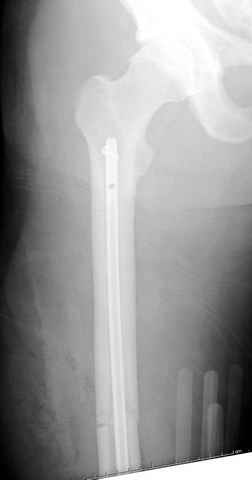

больному 42, автоавария, политравма, открытая черепномозговая травма, безсознании, открытый перелом бедра, размозжение мягких тканей, дефект кожи на передней поверхности бедра около 13 см2 от ожога, компартмент синдром.

По поводу открытого перелома больной ургентно взят на ретроградное интрамедулярное штифтование, после рутинного дебрайдмента и фасциотомии на бедре и на голени.

перелом бедра

интраоперационные

постоперационные